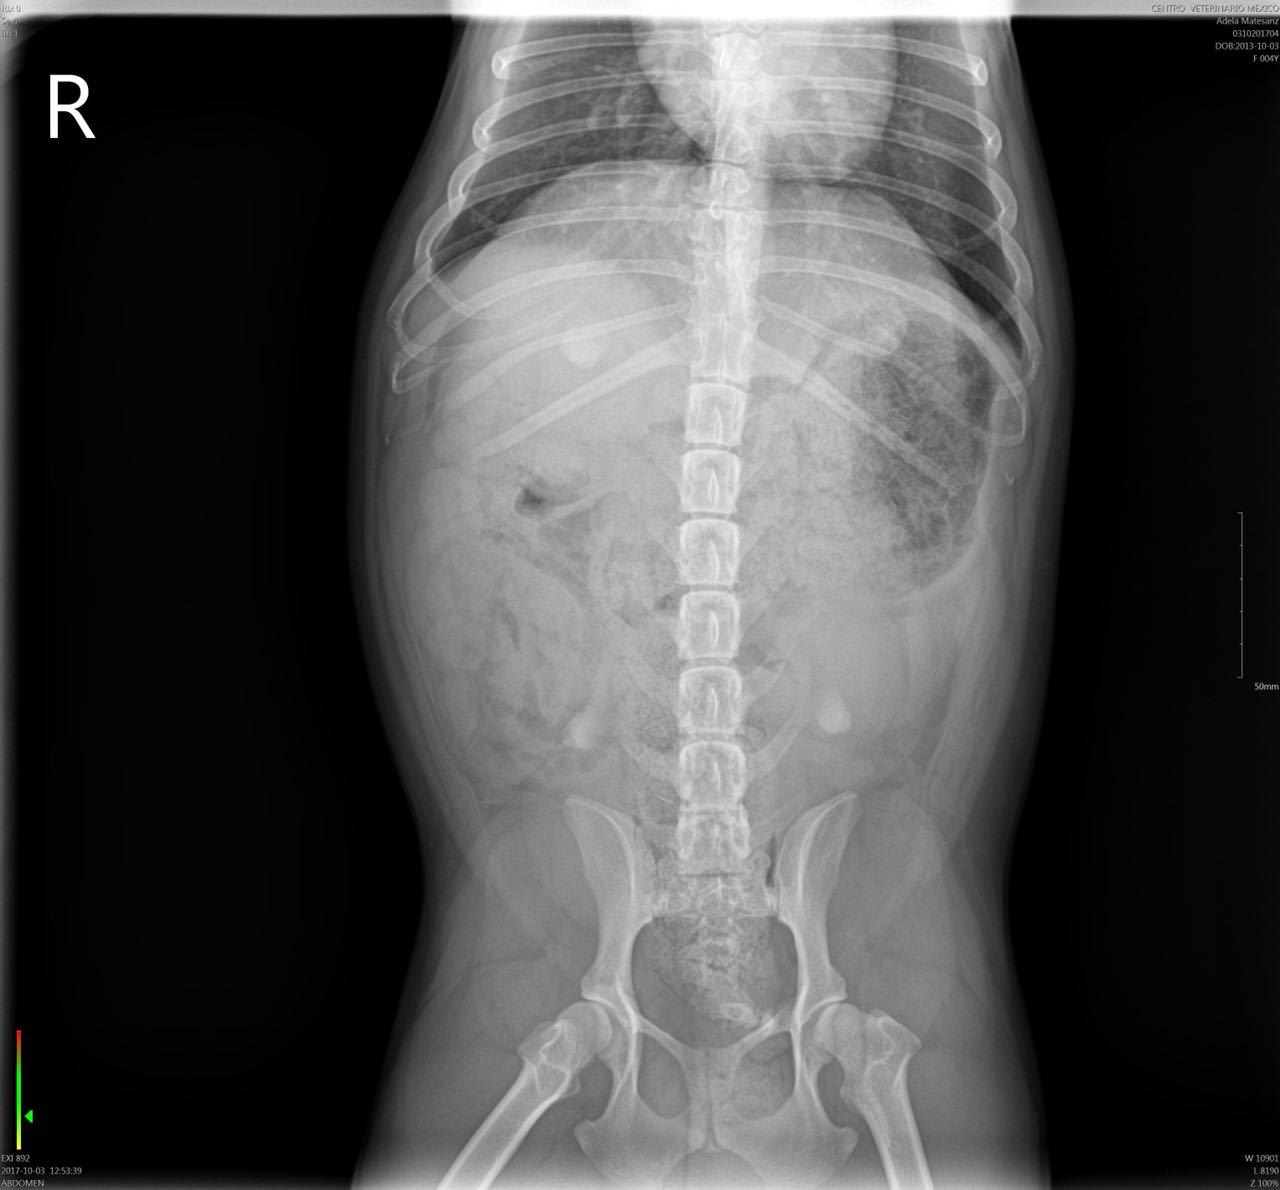

Hello, my dog was chewing on a pork rib bone yesterday and i think i got most of it out, she's a 4 year old french bulldog not spayed, i gave her a slice of bread right after soaked in olive oil and she puked it, took her to the vet they got xrays she was hacking and coughing this morning the xrays dont show a blockage but she ate today and puked all her food and part of yesterdays i checked there were no bones or anything solid in the vomit, she has also been pooping fine